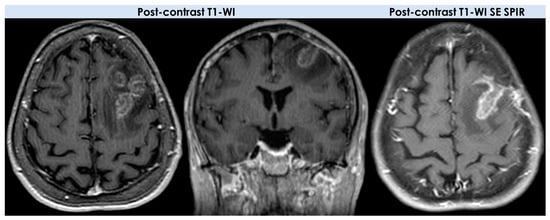

- Enhancement patterns (parenchyma): all patients (10/10, 100%) had enhancing lesions with patchy parenchymal pattern in 5/10 (50%), “mottled appearance” (multiple small hypoenhancing areas within the patchy enhancing masses) in 3/10, small nodular pattern in 5/10, ring enhancement in 2/10, and linear (perivascular) enhancement pattern in 1/10 patients;

- Enhancement patterns (leptomeninges): localized leptomeningeal enhancement adjacent to the dominant/largest lesions was found in 4/10 patients (40%), localized subependymal enhancement adjacent to the lesions in 3/10 patients (30%); and diffuse leptomeningeal or subependymal enhancement was not documented;

| Contrast enhancement (CE) on T1-WI | Moderate–marked CE Non-AIDS patients: homogeneous CE, 90%; ring CE, 0–13% Leptomeningeal, subependymal, dural, or cranial nerve CE AIDS patients: irregular CE common; ring CE, 75% | Open ring (35%) Closed ring (18%) Homogeneous, heterogeneous, patchy and diffuse, cotton ball, and nodular patterns (NMOSD lesions often have absent or minimal enhancement) | Typically ring enhancement | Heterogeneous |